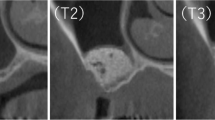

Dental computed tomography

The bone quality of the augmented sinus floor was evaluated in a dental CT of the upper jaw prior to implant placement (Fig. 6). Radiological signs of marginal osseointegration of the graft could be shown. Bone density was assessed by using the Hounsfield classification. The measurements corresponded to a bone quality of Q3 to Q2. There were no radiological signs of inflammation visible. In the region of the roots of the upper jaw, a regular bone structure was found. Also, sinus maxillaris was free of inflammation and was normally ventilated.

The density of the newly formed bone corresponded to a quality of Q2 to Q3 according to the Hounsfield classification, as verified by determination of the specific Hounsfield units by CT scans. This quality of bone can be compared with the local origin trabecular bone and is even denser than the original bone matrix of the posterior maxillary region. This confirms our histologic findings and the stable osseointegration of the implants, which are surrounded by sufficient bone as seen in the postoperative panoramic radiograph.